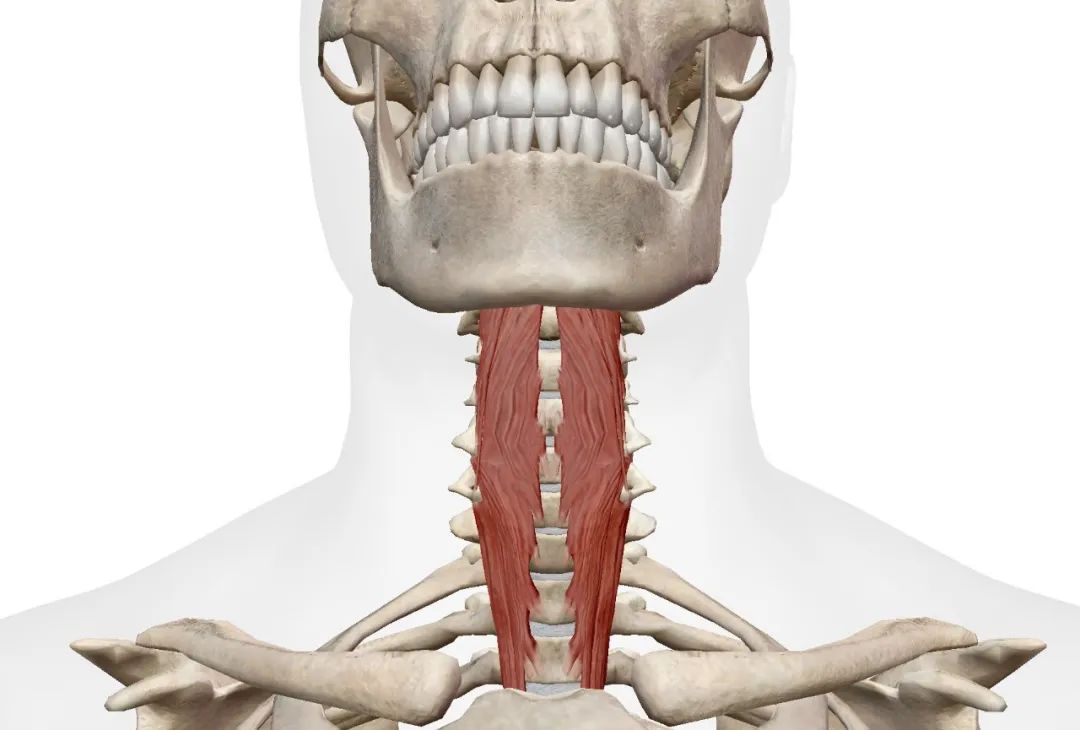

■ 椎旁肌肉: 颈椎周围的肌肉组织,包括颈部的表浅肌肉和深层肌肉,起到支撑颈椎和头部的作用。

恢复期 (又称增生期,5 - 12周)

第五周至第八周:深层颈屈肌训练,这是颈椎稳定最重要的肌肉,可以这么说,它就是颈椎的核心肌群,训练这块肌肉,就好比训练躯干部位的核心力量。加强深层颈屈肌的力量就是给颈椎保驾护航,如:*疆新**舞,贴墙收下巴都是不错的颈椎稳定训练。